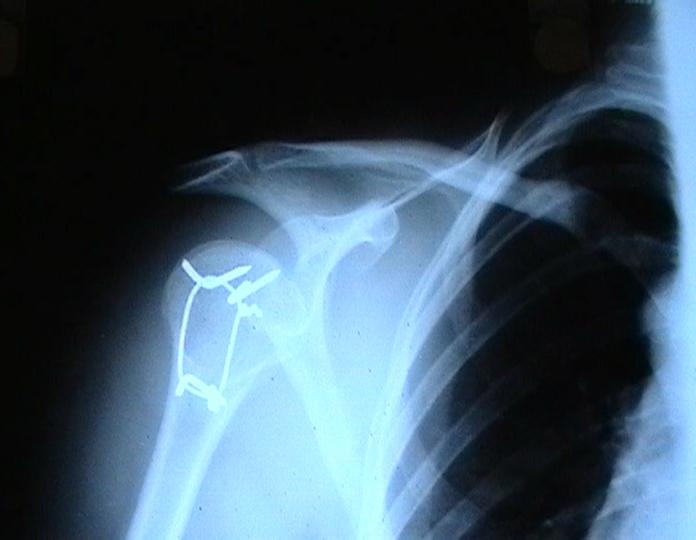

Переломовывих плеча сложная проблема и технически не уверен как для коллег, но для меня сколько я не встречался, технически сложно *вытянуть* вывихнутую головку из-под впадины. Последнее время не применяю пластины для фиксации перелома, а использую спицы и проволочную петлю (тем более часто и густо спонгиозные винты не держатся в головке прочно).

Момент , который следует учитывать при использовании такого рода фиксации - необходимо быть уверенным , что спицы не проникают в сустав, поэтому полезно пользоваться ЭОпом для контроля или интраоперационными рентгенограммами

перед ушиванием раны.

Фиксация получается достаточно стабильная, правда мои заключения основаны только на клинических наблюдениях, возможности протестировать прочность фиксации в лабораторных условиях нет. Я не автор данного типа фиксации в основе его лежит принцип напряженной фиксации (Weber tension Band fixation). Когда-то у нас использовали фиксатор проф Сеппо при переломах

шейки бедра - принцип работы аналогичен, только менее громоздкие элементы конструкции и более доступные для применения в любых условиях.